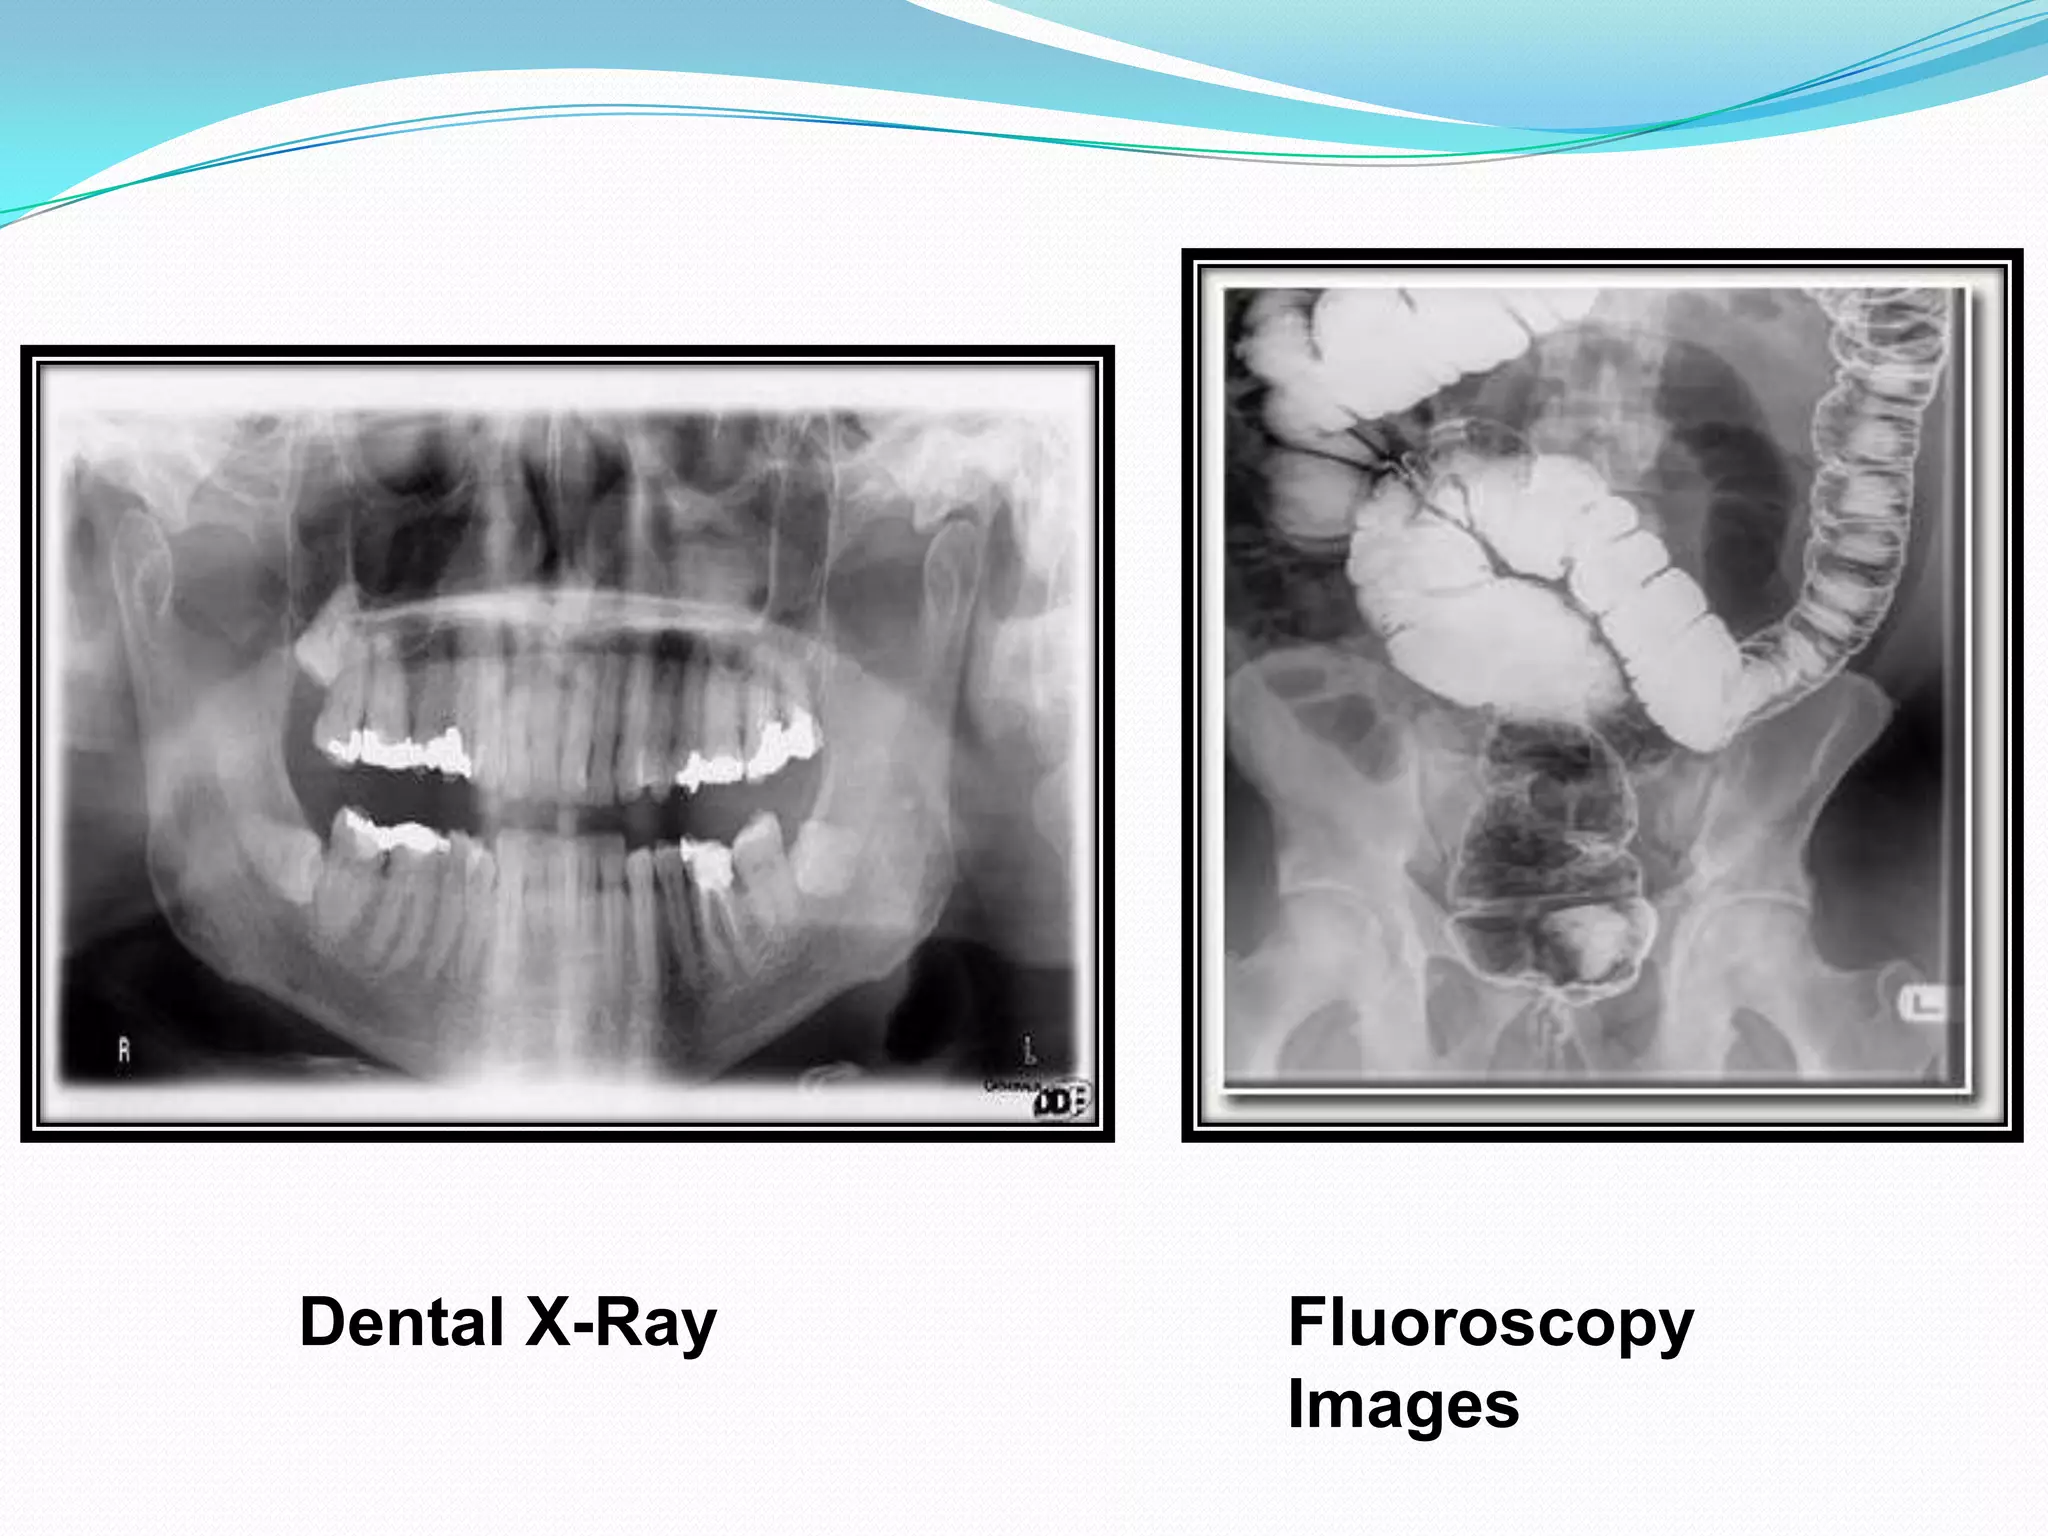

Dental X-Ray Machine   X Ray Fluoroscopy Unit

Dental X-Ray   Fluoroscopy

Images

Dental X-Ray Fluoroscopy Images